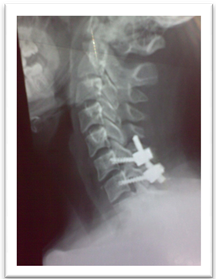

Male patient 36 years old had road traffic accident, with modified Frankel’s grade C and DFI stage 3. Skull traction was applied to restore of cervical alignment. Rapid anterior cervical approach, discectomy, unlocking of the facets, fusion with cervical cage and fixation with plate and screws (Figure 1).

Figure 1. Showing case 1 presentation. (a) Pre-operative plain X-ray (b) pre-operative skull traction (c) MRI cervical spine (d) post-operative anterior cervical cage fusion and plate fixation.